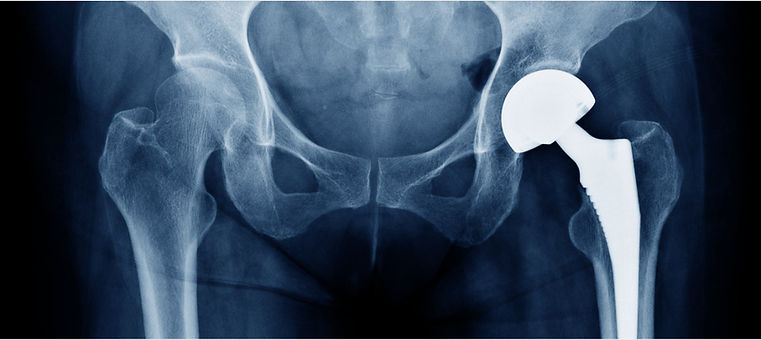

A Multi-Measure, Longitudinal Pain Case Study

This case study explores how a repeat, multi-measure, at-home measurement strategy more clearly characterized pain resolution and functional recovery following total hip replacement by integrating patient-reported outcomes with objective, longitudinal measures.